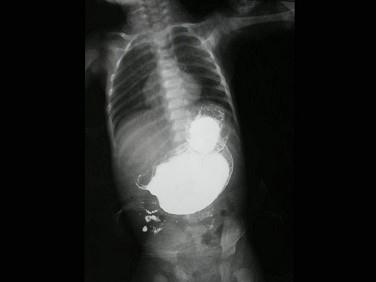

问题 男,6月。出生1月后经常出现喷射状呕吐,为奶块,渐加重。面色消瘦,右上腹部可触及核桃大小硬块。如图,最可能的诊断为?(?)

选项 A.胆总管囊肿 B.肠闭锁 C.先天性幽门肥厚狭窄 D.肠套叠 E.先天性巨结肠

答案 C